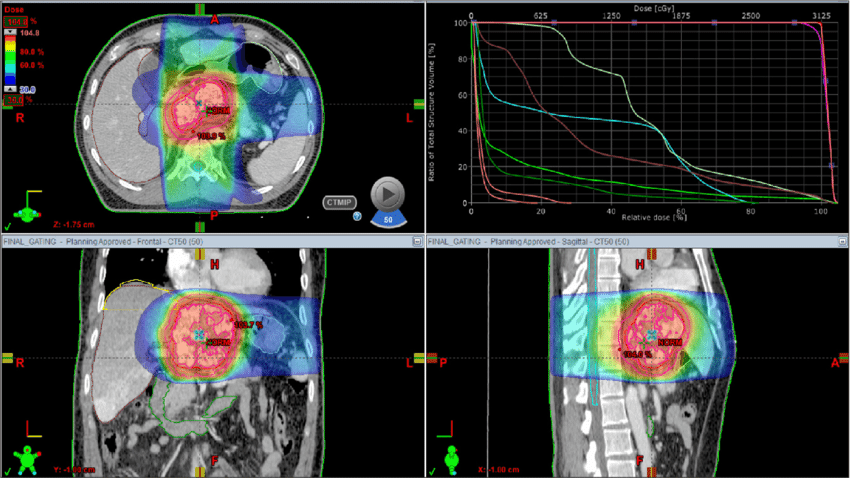

CT 模拟仿真计算模式比较多样,主要有三种特点:

1. 计算量大 涉及大量矩阵运算、投影模拟和迭代优化,尤其在迭代算法中需多次循环(计算量可达TB级数据)

蒙特卡洛模拟需要跟踪数百万到数十亿条光子路径 → 高度并行化

大规模 3D 重建(512³ 体素)在迭代算法下需要数百次前后投影

2. 强依赖并行计算:Forward/Backward 投影高度可并行,GPU 或 CPU 多线程可显著加速

3. 内存与存储需求高

大体积数据(投影矩阵、体数据)动辄数GB~数百GB

GPU显存/内存不足会限制可处理的体素分辨率

4. 噪声与artifact处理:算法需校正散射、噪声和射束硬化,深度学习方法可降低辐射剂量但增加计算复杂度

5. I/O与可视化要求

大量的投影文件和3D重建结果需要高速SSD

可视化时需要显卡具备较强 OpenGL/DirectX 或CUDA能力

6 实时性与精度权衡:解析算法快速(秒级),迭代算法更准但慢(分钟到小时);4D-CT需处理呼吸运动,增加维度导致计算翻倍。